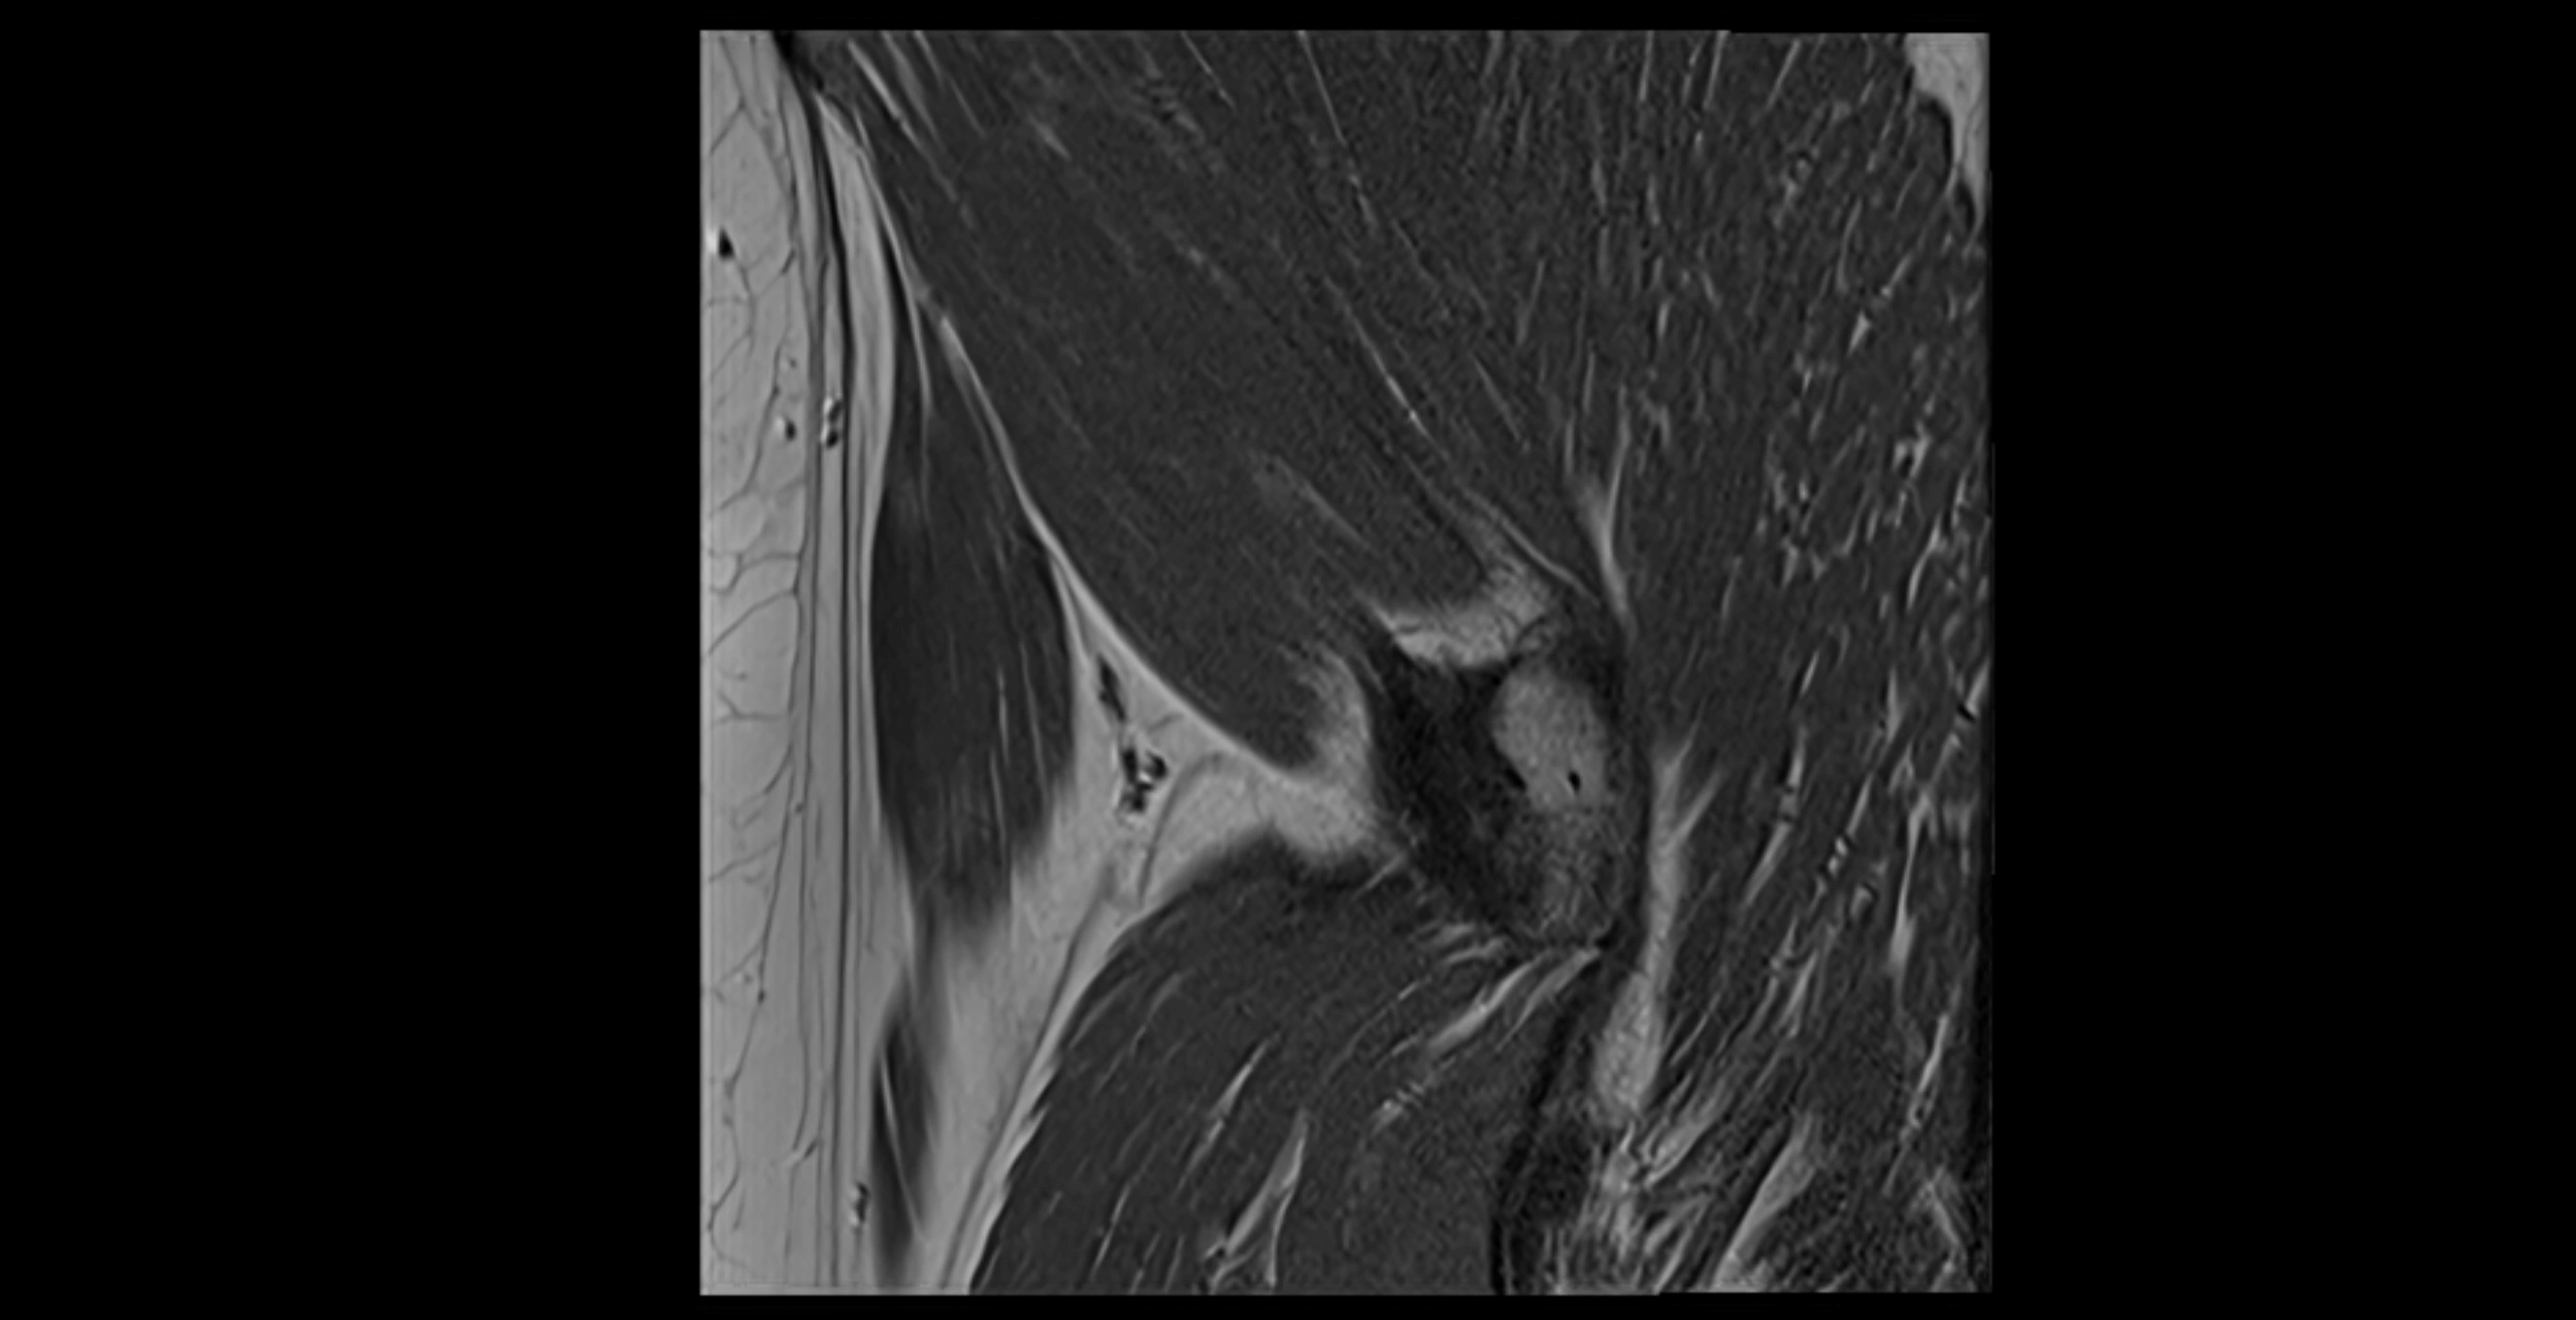

MRI image

image

MRI Appearance

T1-weighted images:

• Labrum: low signal intensity (dark)

• Surrounded by intermediate signal joint fluid (bright on arthrogram)

• Tears: linear or focal areas of intermediate-to-high signal interrupting labral continuity

T2-weighted images:

• Joint fluid: bright, making labral tears visible as fluid extending into or around labrum

• Degeneration: may show areas of increased signal within labrum